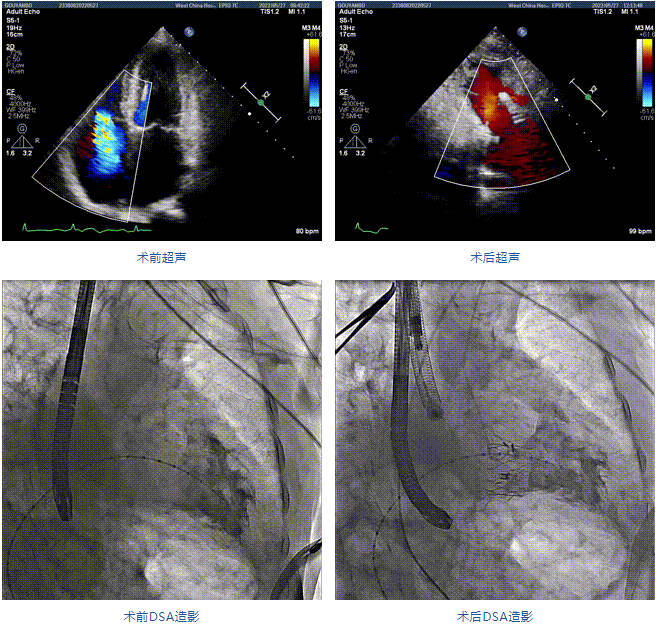

2022年5月27日,四川大學(xué)華西醫(yī)院心臟內(nèi)科陳茂、馮沅教授帶領(lǐng)的瓣膜病介入治療多學(xué)科團(tuán)隊(duì),在國內(nèi)首次采用純介入方式通過穿刺右側(cè)頸靜脈成功完成經(jīng)導(dǎo)管三尖瓣置換。植入的人工瓣膜是具有中國自主知識(shí)產(chǎn)權(quán)的LuX-Valve Plus系統(tǒng)。術(shù)中上海長海醫(yī)院陸方林教授和喬帆副教授給予了在線支持。

患者為89歲高齡男性,罹患三尖瓣反流多年,近期癥狀明顯加重,經(jīng)過充分的藥物治療后仍然存在嚴(yán)重心力衰竭。通過純介入方式實(shí)施三尖瓣置換,使這位超高齡的老人以最小的代價(jià)獲得了有效的治療。介入治療的效果十分滿意,術(shù)后三尖瓣反流消除,老人迅速恢復(fù),心功能明顯改善。該手術(shù)的成功實(shí)施標(biāo)志著國內(nèi)經(jīng)導(dǎo)管三尖瓣置換進(jìn)入純介入時(shí)代。

89歲男性。術(shù)前超聲報(bào)告顯示:雙房增大,左室壁肥厚,主、肺動(dòng)脈增寬,三尖瓣重度反流。

團(tuán)隊(duì)前期經(jīng)過多次討論,制定了周密的手術(shù)策略和預(yù)案。由于患者已是近九旬的超高齡老人,傳統(tǒng)外科開胸手術(shù)風(fēng)險(xiǎn)極高,純介入經(jīng)血管三尖瓣替換能夠明顯減少創(chuàng)傷。術(shù)中陳茂及馮沅教授結(jié)合體表定位在造影指示下精準(zhǔn)穿刺右側(cè)頸靜脈并預(yù)置兩把血管縫合器。成功建立經(jīng)皮血管入路后在食道超聲和DSA的引導(dǎo)下順利完成人工瓣膜植入,術(shù)后超聲和造影顯示人工三尖瓣同軸性良好,瓣架固定牢靠,無反流和瓣周漏,平均跨瓣壓差降為1mmHg。術(shù)畢收緊預(yù)置的血管縫合器縫線完成止血,縫合效果滿意,在手術(shù)室即刻拔除氣管插管。